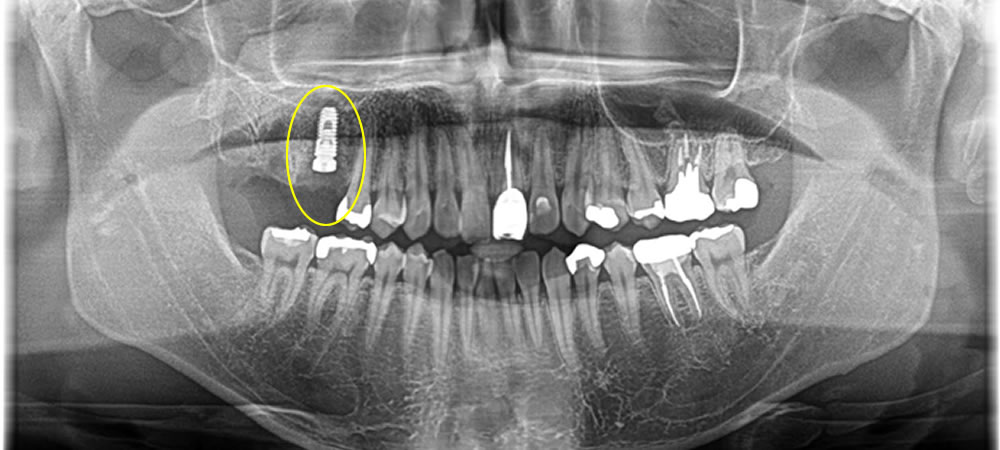

他院で抜歯した部分をインプラントで治療した症例

まずは割れた歯の根が残っていたので除去した後、中の膿が溜まっている所を綺麗にし即時でインプラントを埋入、骨を作る処置までを行いました。

ほっぺた側の骨が無くなっていましたが、しっかりと骨を作る事で歯茎の下がりを最小限に抑えることができました。